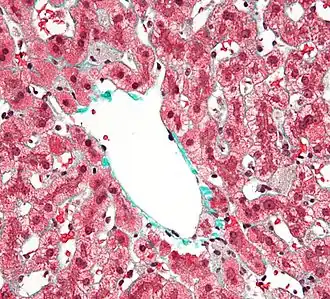

Кле́тки Ку́пфера — специализированные клетки, располагающиеся в люмене (внутреннем пространстве) синусоид печени и прикрепленные к синусоидальным эндотелиальным клеткам, образующим стенки кровеносных сосудов. Клетки Купфера — наиболее многочисленные резидентные макрофаги в печени человека, они входят в состав системы мононуклеарных макрофагов (ретикуло-эндотелиальной системы). Через воротную вену в печень из пищеварительного тракта поступают кишечные бактерии, бактериальные эндотоксины, которые в печени первым делом сталкиваются с клетками Купфера, образующими первую линию иммунной защиты печени. Нарушения функционирования клеток Купфера сопровождают многие заболевания печени, такие как алкогольная болезнь печени, вирусные гепатиты, внутрипечёночный холестаз, стеатогепатит, цирроз печени, а также при отторжении трансплантата печеночной ткани[2][3].

Клетки Купфера имеют амёбоидную форму и прикреплены к синусоидальным эндотелиальным клеткам. На поверхности клеток Купфера имеются микроворсинки, псевдоподии и ламеллоподии, расположенные во всех направлениях. Микроворсинки и псевдоподии задействованы в поглощении частиц. В цитоплазме клеток Купфера располагаются рибосомы, аппарат Гольджи, эндоплазматический ретикулум (в особенности, шероховатый), центриоли, микротрубочки и микрофиламенты. Ядро яйцевидное, может быть подразделено на доли. В органеллах клеток Купфера присутствует пероксидазная активность. Клетки Купфера локализованы и в центрилобулярной, и в перипортальной части долек печени, однако их функции в этих регионах различны. Перипортальные клетки Купфера более крупные, содержат больше лизосом и более активны в плане фагоцитоза, а центрилобулярные клетки Купферы специализированы на генерации супероксид-радикала. Внутри клеток Купфера имеются скэвенджер-рецепторы SR-AI/II. Они участвуют в распознавании и связывании липида A в составе молекул липополисахарида и липотейхоевых кислот. Липополисахарид является эндотоксином, входящим в состав клеточных стенок грамотрицательных бактерий, а липотейхоевые кислоты присутствуют в клеточных стенках грамположительных бактерий[4].

Среднее время жизни клеток Купфера составляет 3,8 суток. Их главная функция — удаление инородного дебриса и частиц, поступающих в печень по воротной вене. Крупные частицы, возможно, поглощаются клетками Купфера с помощью фагоцитоза, а мелкие — посредством пиноцитоза[4]. Клетки Купфера входят в систему врождённого иммунитета и играют важную роль в защите организма, а также метаболизируют различные вещества липидной природы, расщепляют белковые комплексы и мелкие частицы. Они также удаляют из кровотока апоптотические клетки. Количество клеток Купфера в печени постоянно и поддерживается с помощью апоптоза и фагоцитоза соседними клетками Купфера. Они обладают пролиферативным потенциалом и могут восстанавливать свою численность, в отличие от макрофагов, происходящих от моноцитов, которые неспособны к пролиферации. По функциям клетки Купфера гетерогенны, и клетки из разных локаций могут отличаться функционально. Например, клетки Купфера из зоны 1 дольки печени более активны, чем таковые из зоны 3, вероятно, в связи с тем, что клетки из зоны 1 больше сталкиваются с чужеродными частицами и веществами. Клетки Купфера могут продуцировать провоспалительные цитокины, в частности, фактор некроза опухоли α (TNFα) в M1-состоянии, и противовоспалительные цитокины, например, IL-10, в M2-состоянии, кислородные радикалы и протеазы. Выделение этих соединений может приводить к повреждениям печени[4]. Кроме того, клетки Купфера несут рецепторы комплемента иммуноглобулинового семейства (CRIg), и мыши, лишённые CRIg, неспособны разрушать патогенные клетки, покрытые компонентами системы комплемента. CRIg консервативны у человека и мышей и играют важную роль в работе врождённого иммунитета[7].